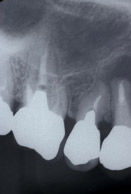

レントゲンで見ると根の先に大きな病気(根尖病変)があり、また歯自体も割れてしまっています。

| レントゲン像です。 大きな根の病気ができています |